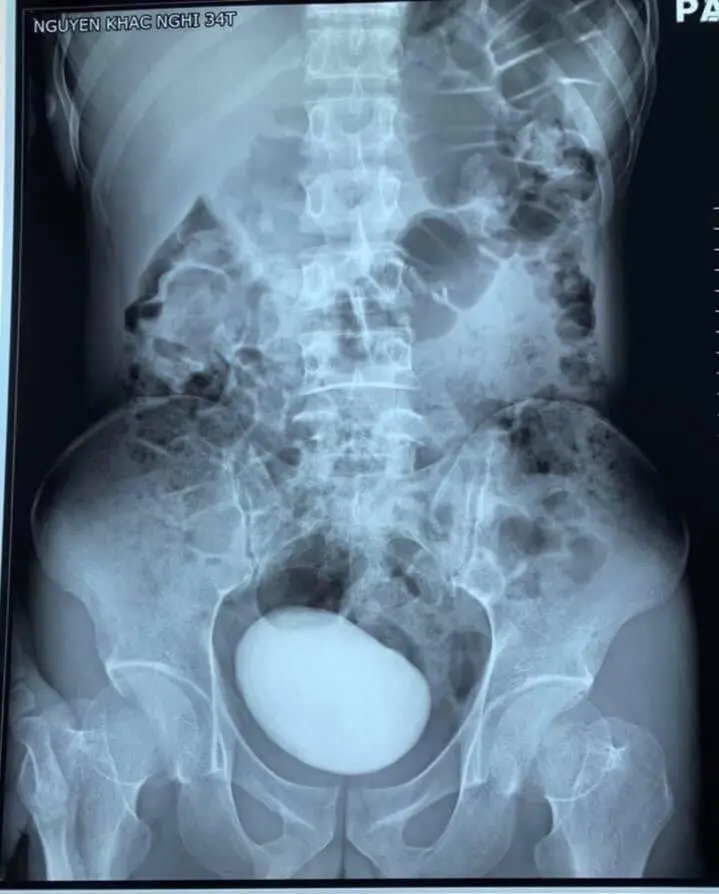

أجرى الأطباء فحصا بالأشعة المقطعية، أظهرت وجود كتلة ضخمة مستديرة في مثانة السيدة التي تبلغ من العمر 34 عاما وبالفعل تمكن الأطباء من إزالة الحصوة التي يزيد طولها عن 10 سم وتزن 400 غرام.

ونشر العديد من الصحف الفيتنامية صور الأشعة المقطعية التي توثق وجود الحجر الضخم داخل مثانة السيدة وصورة ممرضة وهي تلتقط صورة مع الحجر العملاق لتشير إلى ان هذا الحدث نادر الحدوث داخل المستشفى.